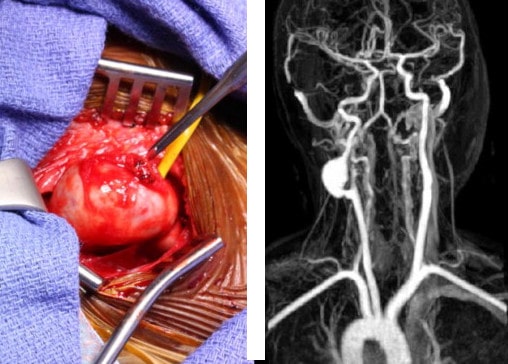

Деформацию аневризмы сонной артерии лечат сосудистые хирурги. Единственно действенный метод лечения — хирургическое вмешательство, которое «отсекает» пораженный участок от кровотока. Тип операции зависит от возраста пациента, состояния здоровья, наличия сопутствующих заболеваний и течения основной патологии.

Полное удаление аневризмы и замена пораженного участка пластиковым протезом или фрагментом кровеносного сосуда с другой части тела. Благодаря этому полностью восстанавливается открытие сонной артерии.

Во время операции концы артерии изолируют, сдавливают резиновыми трубками, вскрывают мешок аневризмы, удаляют пораженные стенки сосуда, а образовавшийся дефект заменяют искусственным. Целостность вен сохранена. Если аневризма больше 5 см, весь пораженный участок артерии удаляется и на его место имплантируется резиновый шланг.

Эндоваскулярные методы используются при небольших аневризмах в труднодоступных местах. Операция проводится внутри сосуда с помощью специального катетера. Это малоинвазивный метод, требующий всего одного небольшого разреза на шее, через который катетер вводится в сосуд. Ангиохирургическая оптика используется для удаления поврежденного участка артерии и замены его другим.